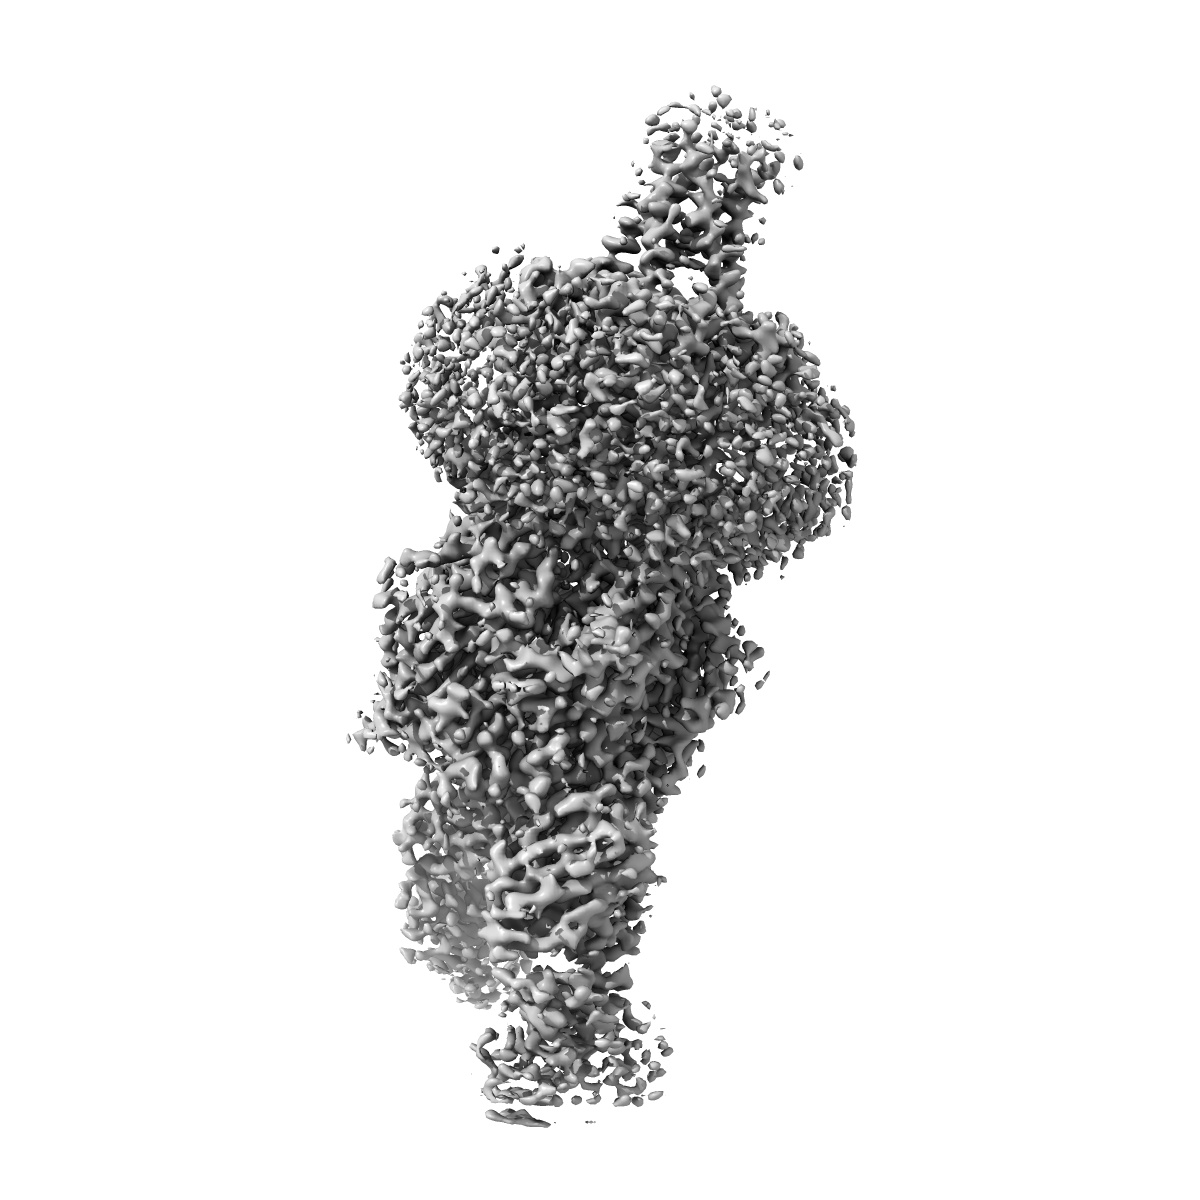

Human alpha3beta4 nicotinic acetylcholine receptor in complex with AT-1001

Sample: Human alpha3beta4 nicotinic receptor in complex with Fab fragments and bound to AT-1001

Agonist Selectivity and Ion Permeation in the alpha 3 beta 4 Ganglionic Nicotinic Receptor.